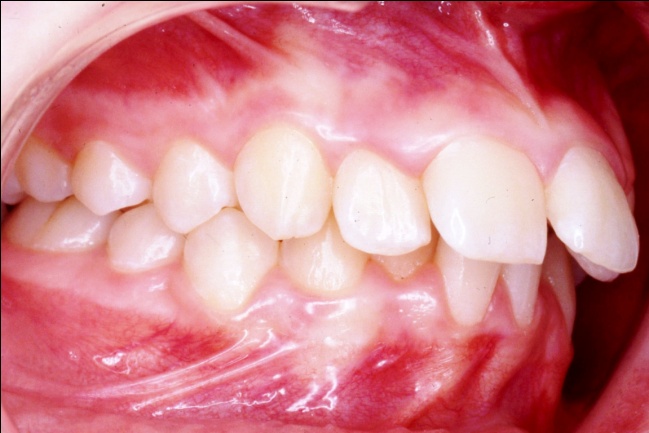

1 - Arcades dentaires avant-après traitement

Les photos montrent, avant traitement, des dents supérieures projetées vers l’avant et encombrées. Après traitement, les arcades, ayant subi l’extraction de prémolaires, présentent un articulé redevenu normal et un alignement complet. Ce résultat positif ne reflète pourtant pas toute l’ampleur des changements : en orthodontie, les dents soutiennent directement les lèvres, et toute modification de leur position influence le profil. Ici, le repositionnement dentaire a eu un effet déterminant sur l’harmonie des tissus mous.